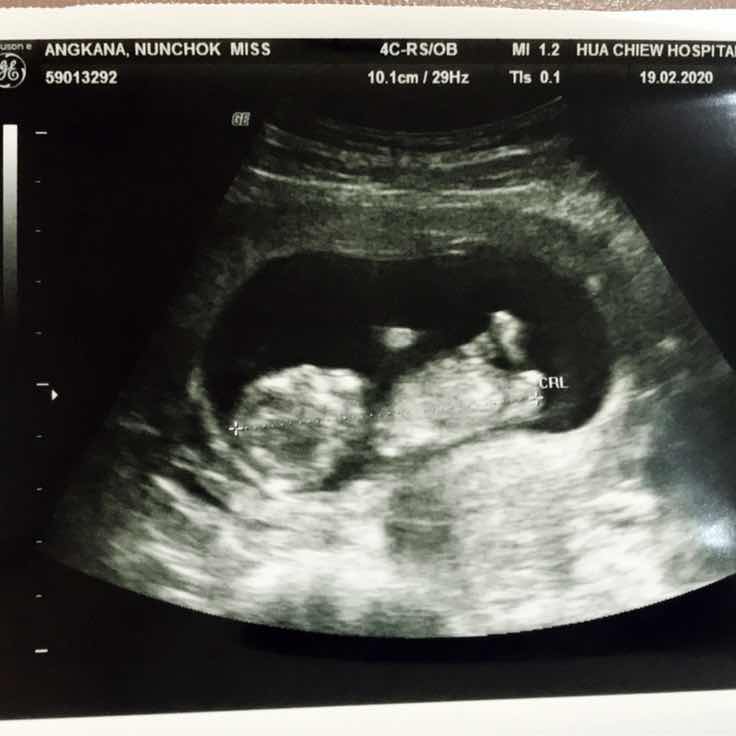

15W2dค่ะ

Post reply image